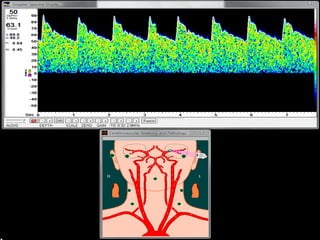

DIA 1 HSA DIA 9 HSA DIA 14 HSA

Seguimiento vasoespasmo

DIA 1 HSADIA 9 HSA DIA 14 HSA Seguimiento vasoespasmo